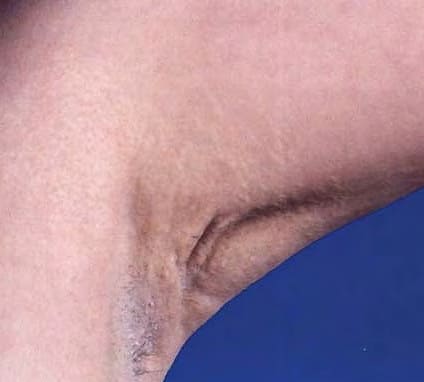

The cutaneous lesions usually appear first in the second or third decade of life and are generally progressive in extent and severity. They consist of soft, yellowish, coalescing papules, and the affected skin appears loose and wrinkled. The sides of the neck, the axillae, and the groin are the most common sites of lesions . In the eyes, so-called angioid streaks of the fundi may cause progressive impairment of vision. Involvement of the arteries of the gastric mucosa may lead to gastric hemorrhage; involvement of coronary arteries may result in attacks of angina pectoris, although myocardial infarction is rare; and involvement of the large peripheral arteries may cause intermittent claudication . Radiologic examination in such cases reveals extensive calcification of the affected peripheral arteries . |